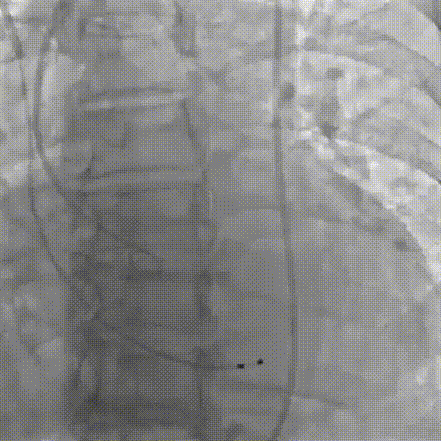

2026年伊始,TaurusTrio经导管主动脉瓣系统在复旦大学附属中山医院,浙江大学医学院附属第二医院,中国医学科学院阜外医院,首都医科大学附属北京安贞医院,四川大学华西医院等多家临床中心成功开展上市后全国首批植入。这不仅是TaurusTrio正式走向广泛临床应用的重要里程碑,更标志着中国单纯主动脉瓣反流介入治疗正式迈入了“心键合璧”的全新纪元。